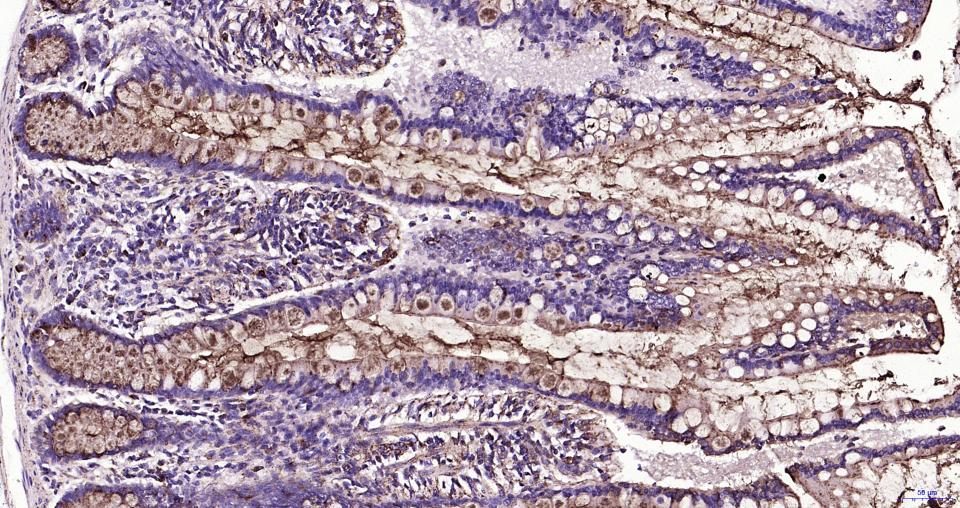

Paraformaldehyde-fixed, paraffin embedded Human Colon Cancer; Antigen retrieval by boiling in sodium citrate buffer (pH6.0) for 15 min; Antibody incubation with LAMP1 Monoclonal Antibody, Unconjugated(bsm-61375R) at 1:200 overnight at 4°C, followed by conjugation to the SP Kit (Rabbit, SP-0023)and DAB (C-0010) staining.